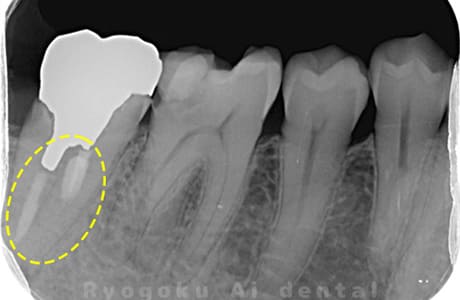

Case02

- 原因

- 慢性根尖性歯周炎

- 治療期間

- 3ヶ月

- 治療内容

- マイクロエンド

- 治療費用

- 121,000円

噛むと痛みが出る、とのことで来院した患者様です。他院での根管治療を終えてましたが、根尖病変を認めるため、マイクロエンドを行いました。

<リスク・副作用>

術後は痛み、腫れ、痺れなどの副作用が生じる場合があります。症状が再発する可能性があります。